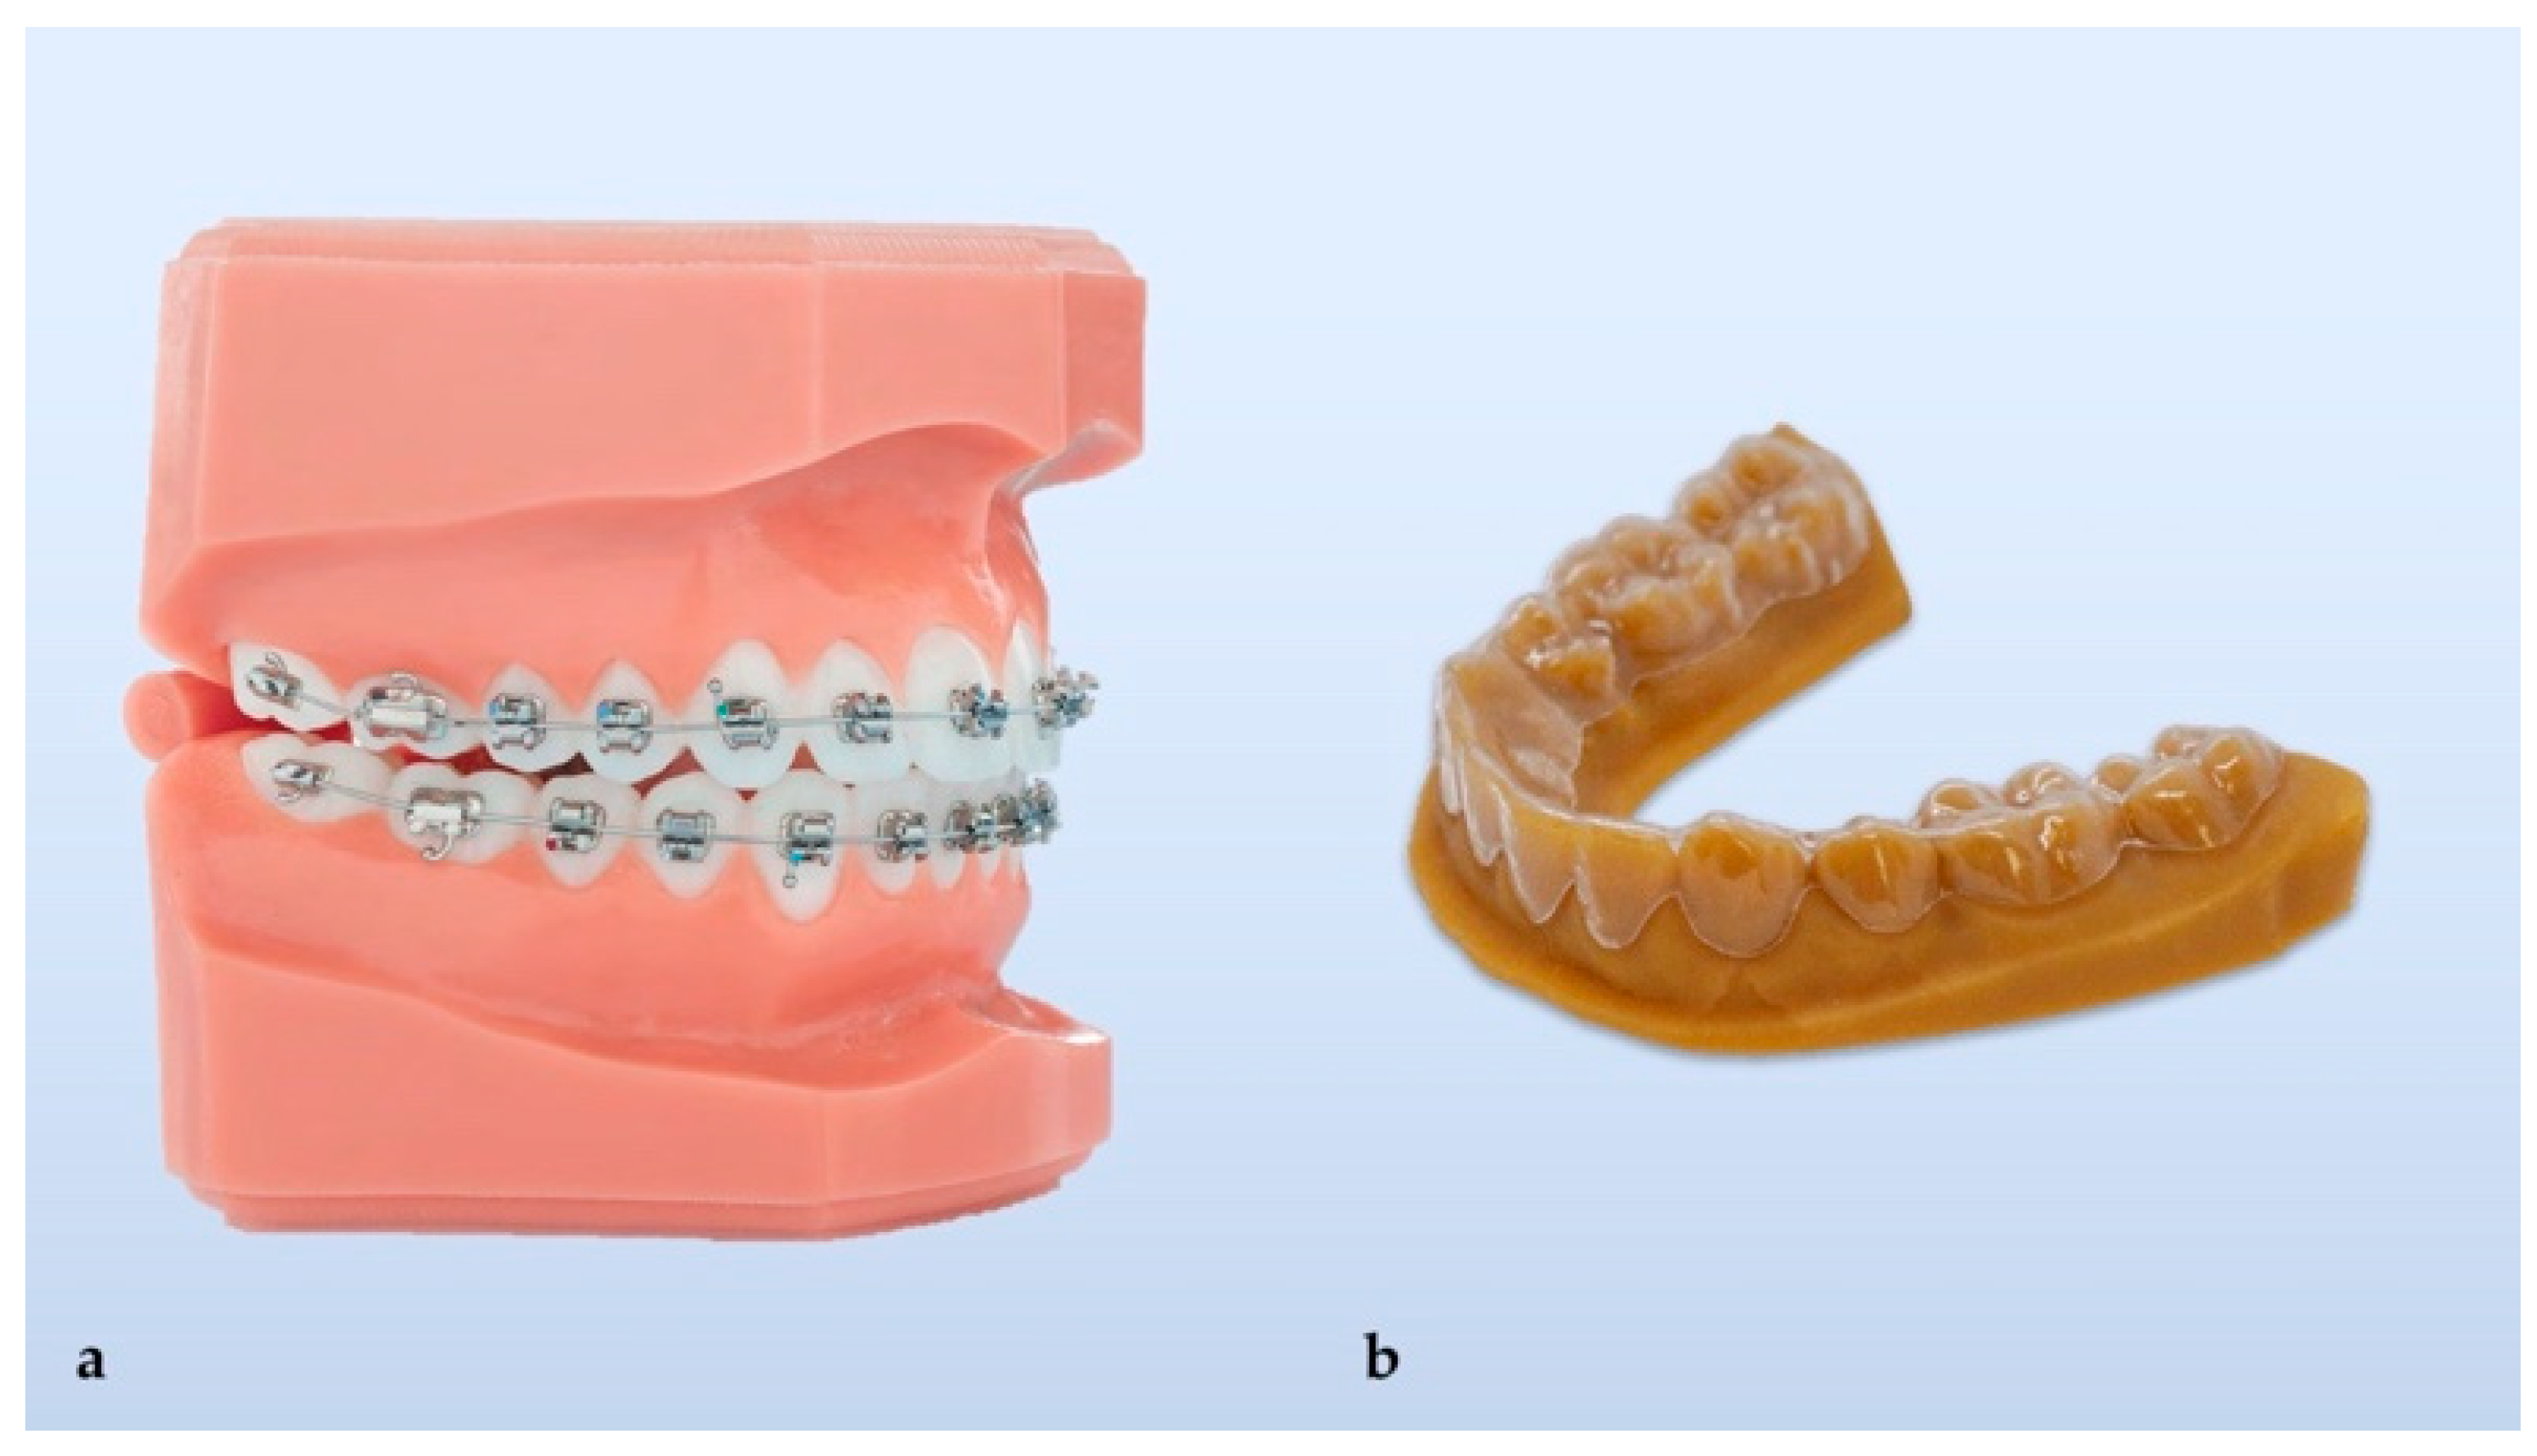

2.1. Development of Clear Aligners- Thermoforming

2.3. Development of Clear Aligners- 3D Printing